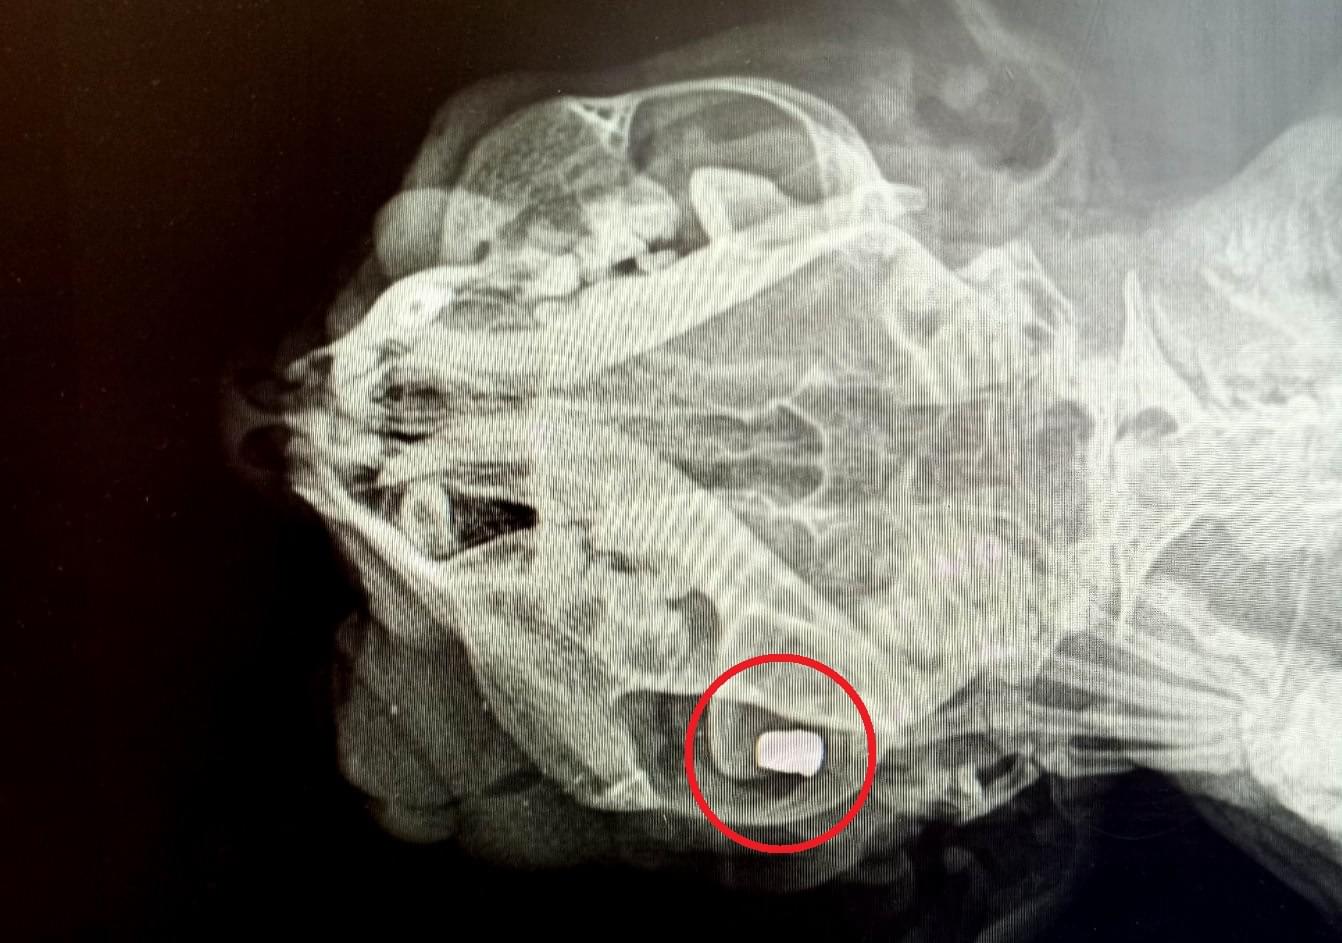

Při vyšetření bylo zjištěno, že Cecilka nejenže přišla o oko následkem střely ze vzduchovky, která jí navíc uvízla v lebce, ale další projektil pak rentgen ukázal ještě v oblasti břicha zvířátka.